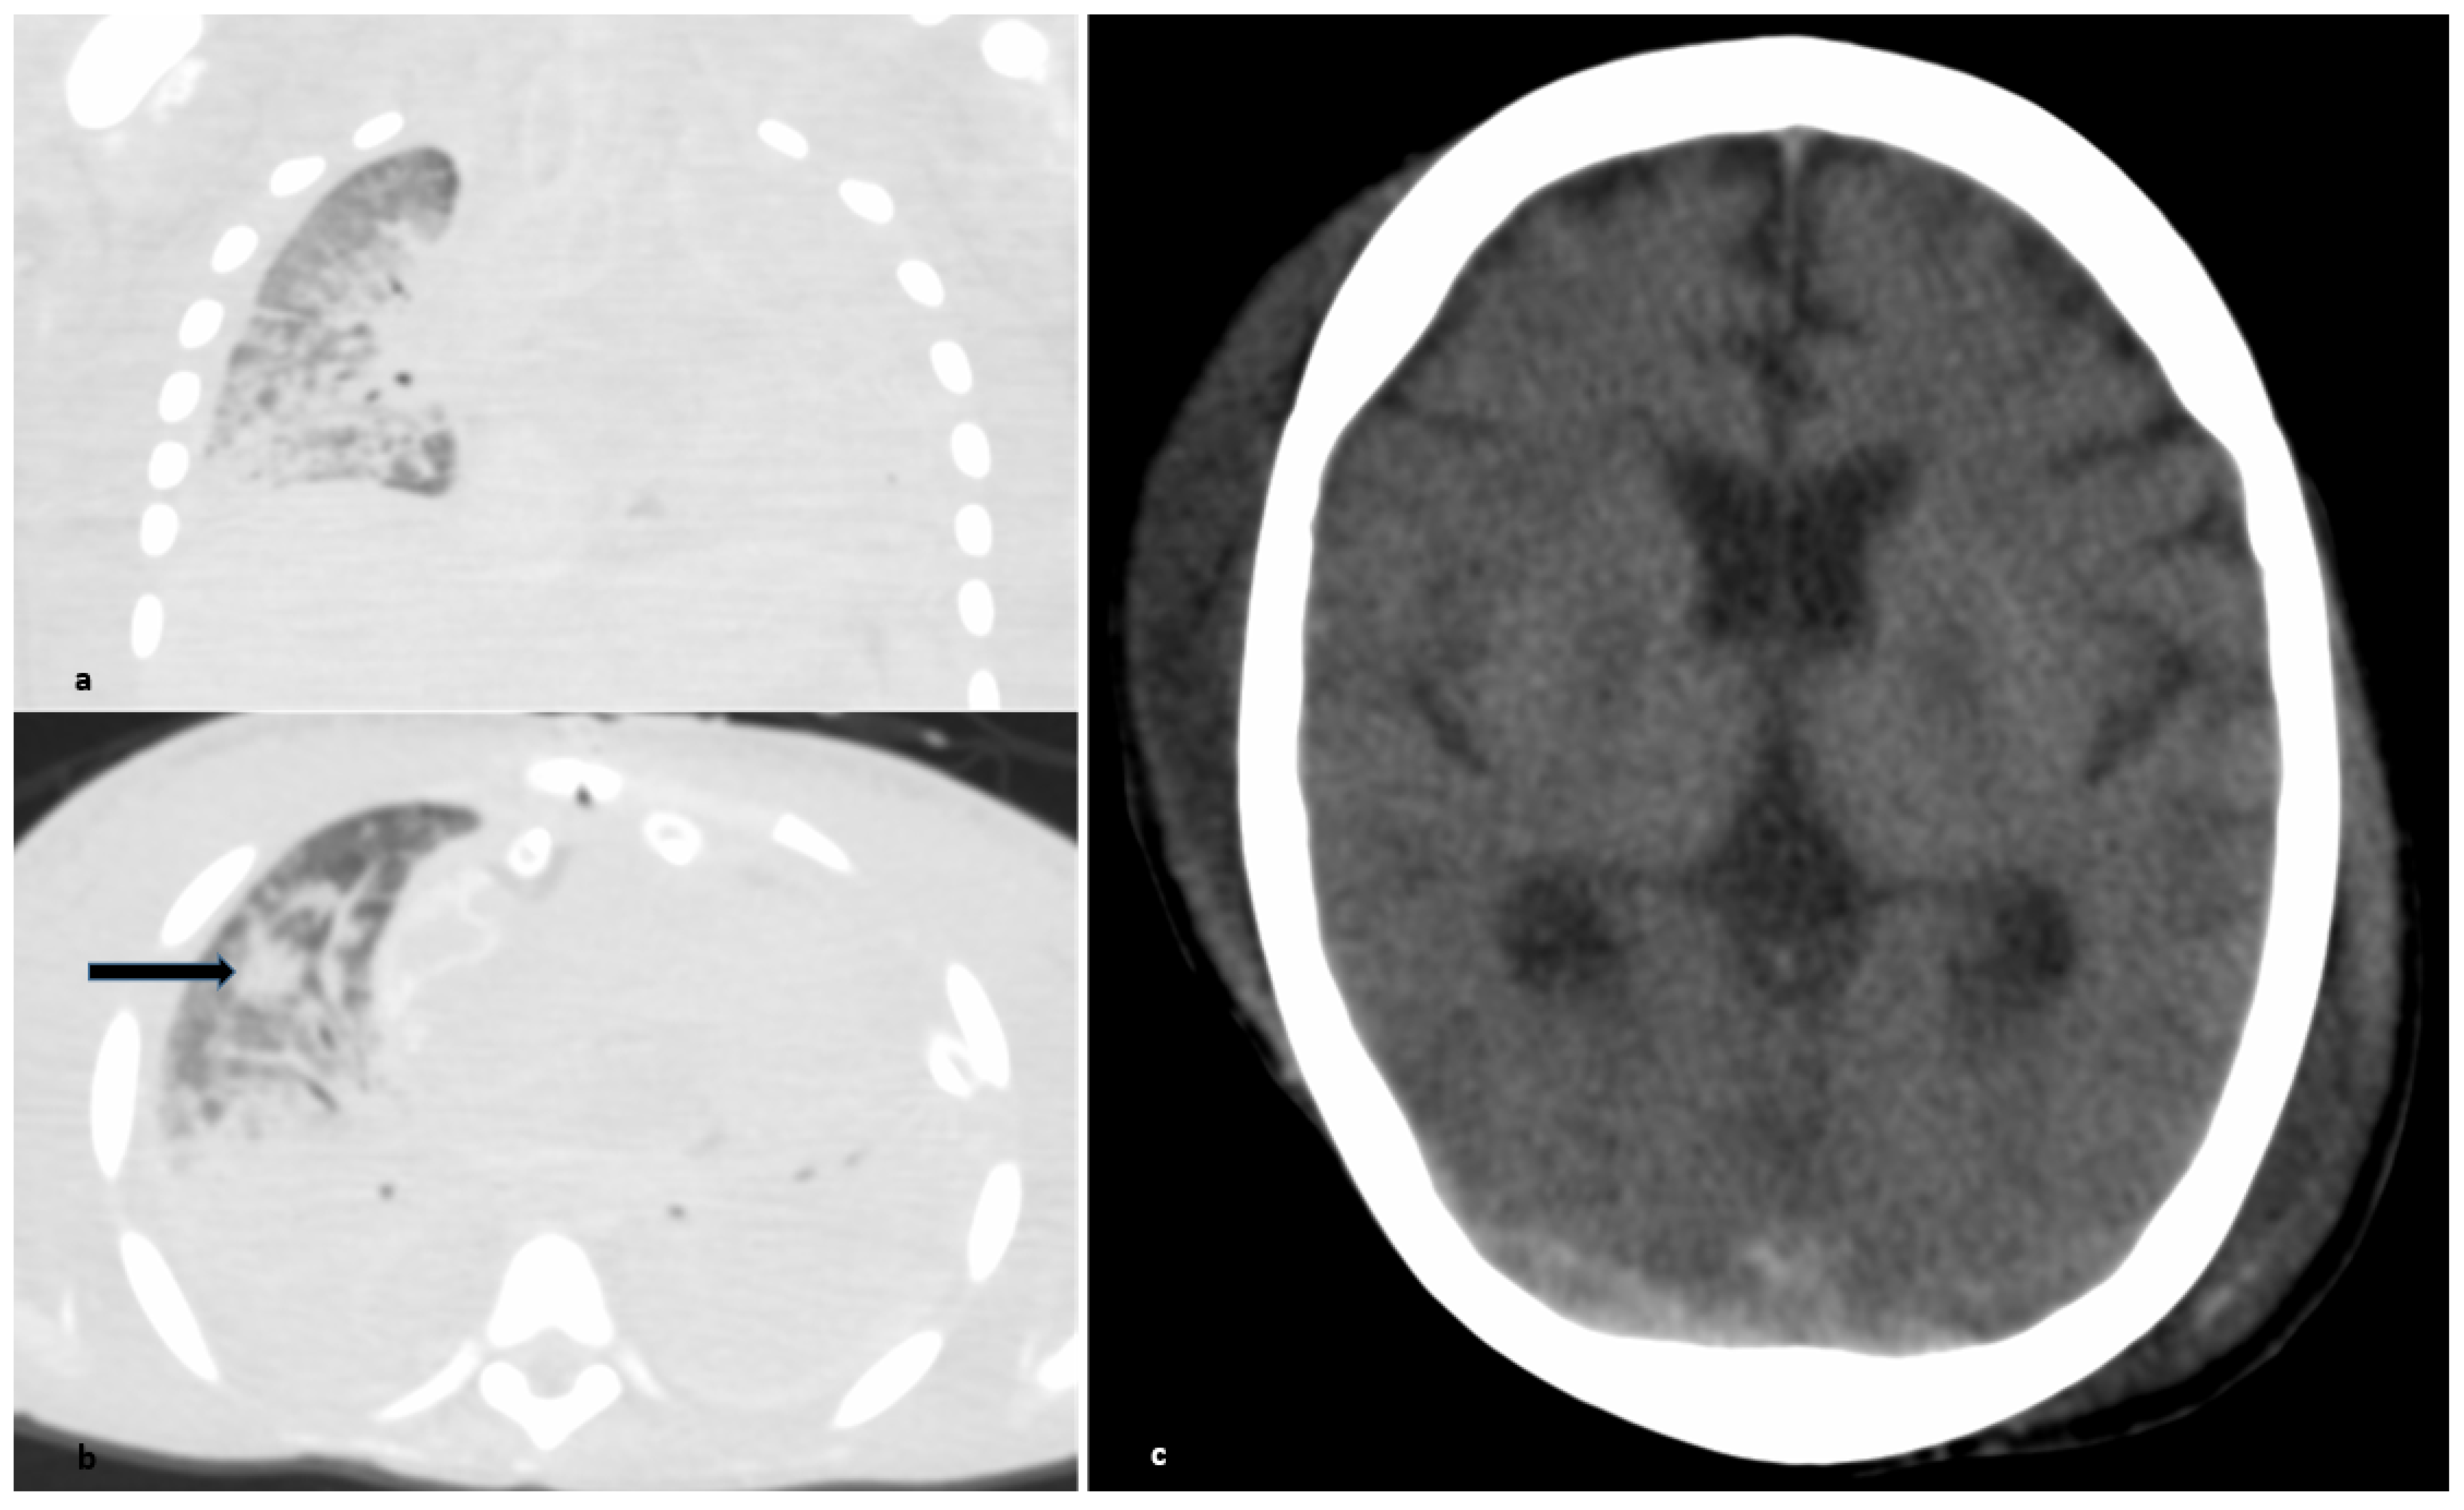

2.1. Respiratory and Cardiovascular System

- Kniep, I.; Lutter, M.; Ron, A.; Edler, C.; Püschel, K.; Ittrich, H.; Heller, M.; Heinemann, A. Postmortale Bildgebung der Lunge bei COVID-19-Todesfällen [Postmortem imaging of the lung in cases of COVID-19 deaths]. Radiologe 2020, 60, 927–933. [Google Scholar] [CrossRef]